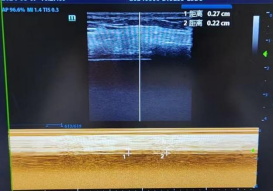

“对于这类多发伤合并ARDS的患者,手术成功只是治疗的第一步,能否安全脱机拔管,直接关系到患者的康复效果和生命安全。”综合ICU一区负责人介绍,长期使用呼吸机不仅会增加肺部感染的风险,还会导致患者呼吸肌萎缩,形成“依赖呼吸机—呼吸肌衰退—无法脱机”的恶性循环,困难脱机、拔管失败是重症患者救治过程中的重点和难点。膈肌超声便是 ICU 床旁无创评估呼吸肌功能的 “得力助手”,尤其对脱机困难患者,能快速定位病因、指导治疗。

膈肌超声评估患者呼吸肌功能

面对患者的救治难题,ICU团队迅速启动困难拔管专项管理流程,依托筹建中的重症困难撤机中心的核心优势,为患者制定了个体化精准脱机方案。团队通过床旁超声实时监测和呼吸机力学数据精准分析,全面评估患者的膈肌功能与肺复张潜力,反复核对各项监测数据,避免盲目脱机,保障脱机过程安全可控;尽管患者身上带有多根引流管和固定支架,行动不便,呼吸治疗师与康复师仍每日协助患者进行床旁坐起、脚踏车训练等早期活动,开展呼吸肌肌力训练,逐步恢复患者呼吸功能;采用自主呼吸试验(SBT)与无创通气序贯支持模式,为患者呼吸肌提供恢复时间,平稳实现从有创通气到无创通气、再到高流量氧疗的过渡,确保每一步治疗都科学严谨。